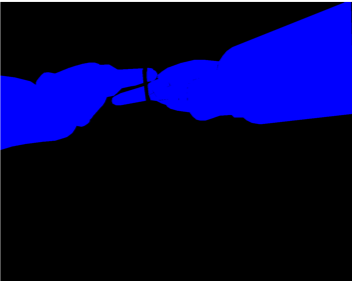

Our challenge was made up of 3 sub-problems. The first was binary instrument segmentation, where each frame was separated into da Vinci Xi instruments and a background class, which contained an ultrasound probe, surgical clips and porcine tissues. The second task was instrument part segmentation, where we scored the participants on whether they could correctly segment each articulating part of the instrument (see Fig. 3). Our final task was to segment and classify the instruments (see Fig. 4).